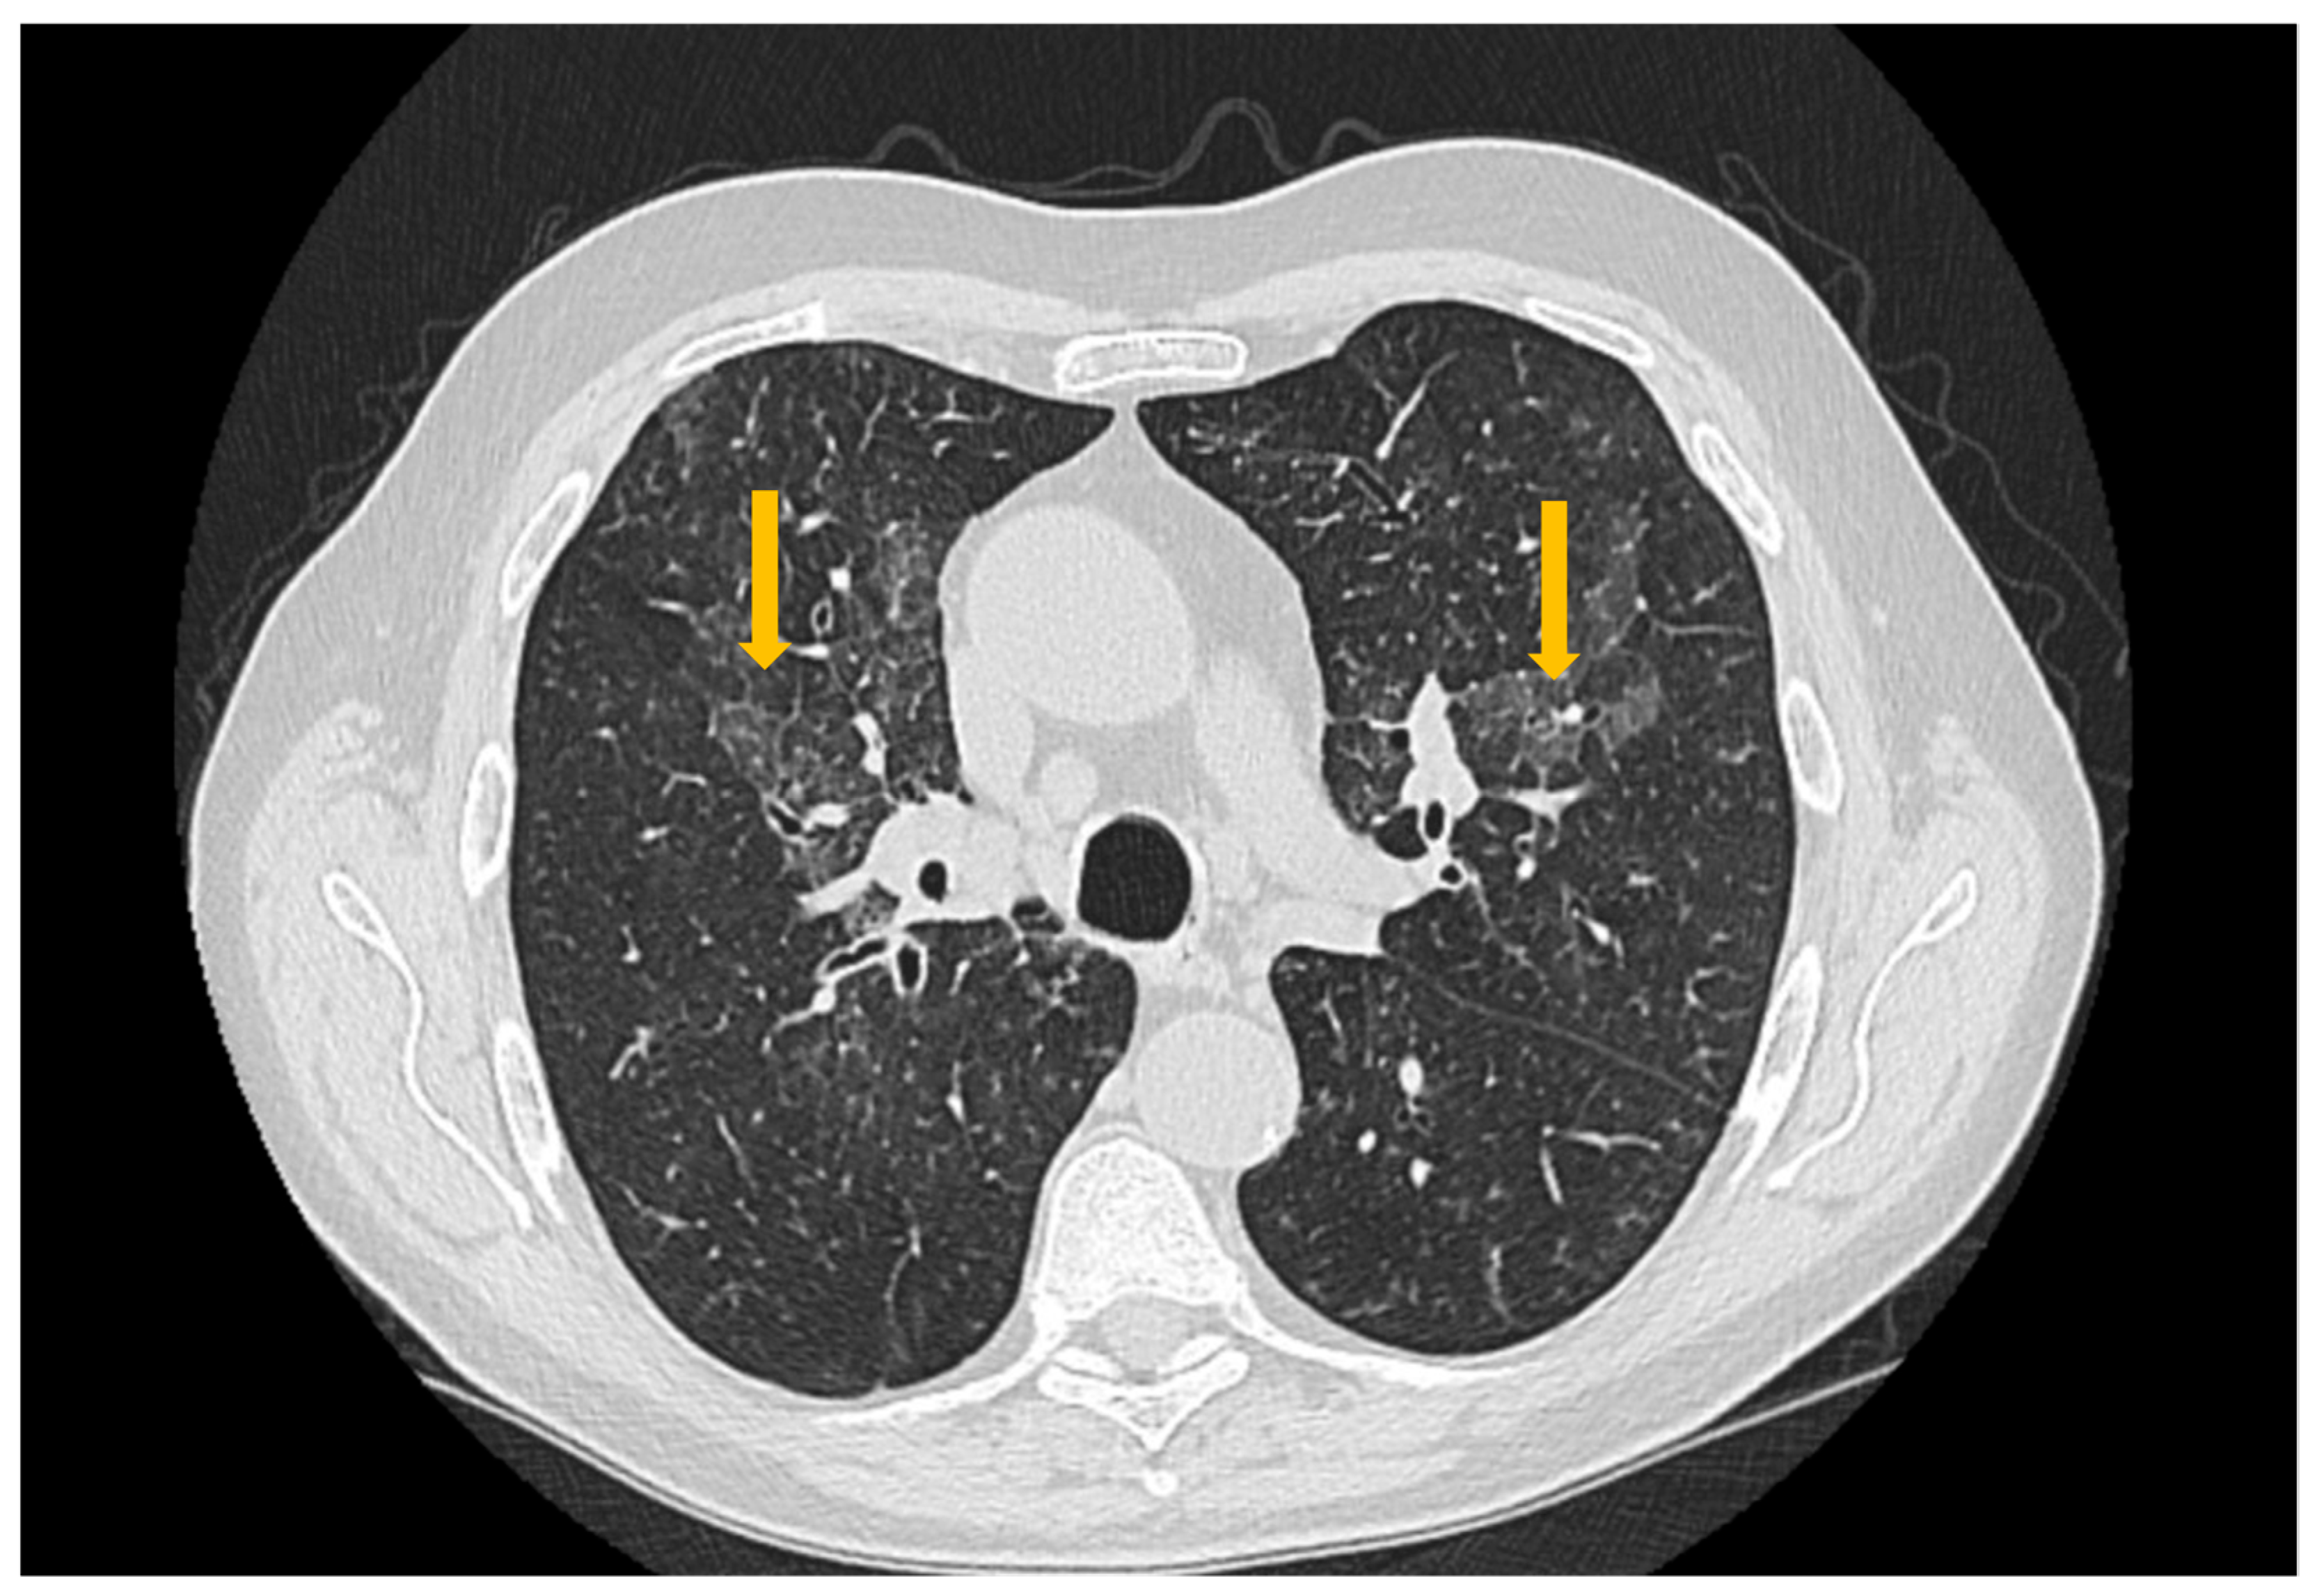

Figure 3. High-resolution computed tomography (HRCT) of the chest in non-specific interstitial pneumonia (NSIP). Axial HRCT image demonstrates bilateral, diffuse ground-glass opacities (arrows), associated with interlobular septal thickening and traction bronchiectasis, findings characteristic of fibrotic NSIP.

High-resolution computed tomography represents the gold standard for evaluating pulmonary changes in diffuse interstitial lung diseases [48]. This imaging technique has a sensitivity of 100%, specificity of 82%, positive predictive value of 97%, and negative predictive value of 100% for the diagnosis of diffuse interstitial disease [49]. The imaging features vary according to the histologic subtype of involvement (Figure 3, Figure 4 and Figure 5) [50].